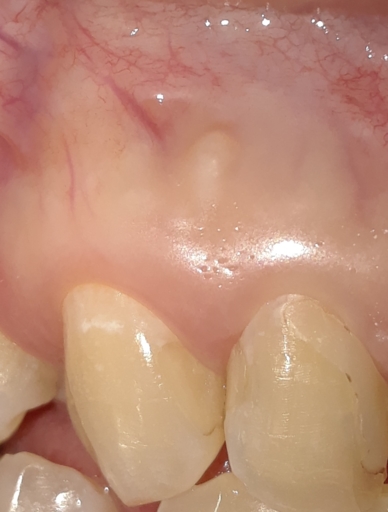

I just went to the dentist because I had fallen and hit my teeth hard. From the X-ray they determined that the nerves in my front two incisors were dead. There was no visible root in either tooth. He didn’t prescribe any treatment because he said the tooth had performed it’s “own root canal”. Is that possible? Should I got back and talk about doing a root canal? There is a little sensitivity in one of the teeth but it’s not debilitating. Should I just wait until the tooth is infected to treat it? I just need some answers. Thanks!

I just went to the dentist because I had fallen and hit my teeth hard. From the X-ray they determined that the nerves in my front two incisors were dead. There was no visible root in either tooth. He didn’t prescribe any treatment because he said...